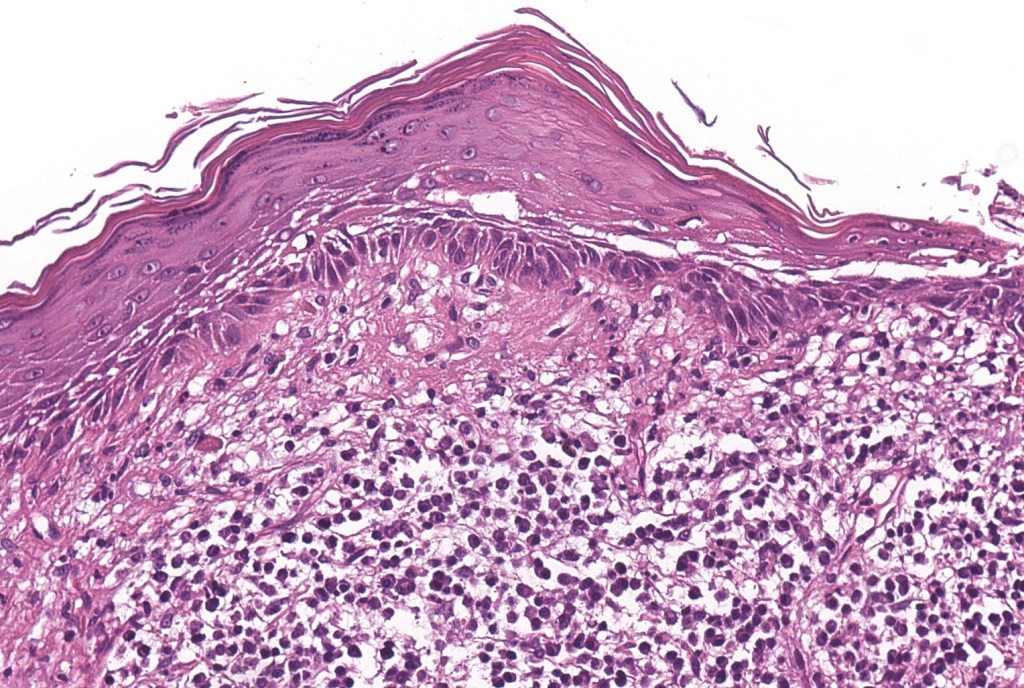

•Actinic lichenoid keratosis

.Superficial dermal lymphohistiocytic infiltrate